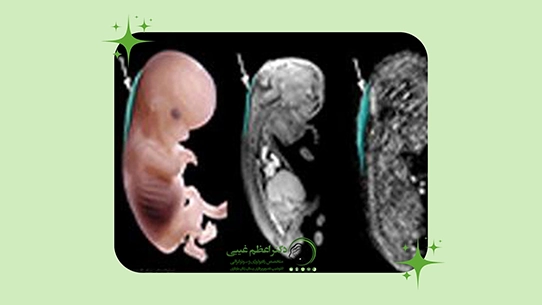

عکس جنین سندرم داون در سونوگرافی

تصاویر سونوگرافی نقش بسیار مهمی در تشخیص سندرم داون دارند. پزشک میتواند با مشاهده ویژگیهای ظاهری جنین و شاخصهای ژنتیکی، احتمال وجود سندرم داون را ارزیابی کند.

برخی از شاخصهای قابل مشاهده در تصاویر سونوگرافی شامل:

- ضخامت پشت گردن (NT): یکی از معیارهای اصلی است.

- استخوان بینی (NB): کوچک بودن یا عدم وجود استخوان بینی نشانه مهمی است.

- فاصله بین چشمها و شکل گوشها: تغییرات ظریف میتواند شاخصهای سندرم داون باشد.

- حرکات دست و پا: برخی ناهنجاریها در حرکات اندامها قابل مشاهده است.

با استفاده از سونوگرافی سه بعدی و چهار بعدی، پزشک میتواند تصاویر دقیقتر و واضحتری از جنین دریافت کند. این تصاویر نه تنها در تشخیص سندرم داون موثرند، بلکه والدین نیز دید بهتری نسبت به وضعیت جنین پیدا میکنند. در نتیجه، تشخیص سندرم داون با سونوگرافی به کمک عکسهای دقیق جنین امکان پذیر و قابل اعتماد است.